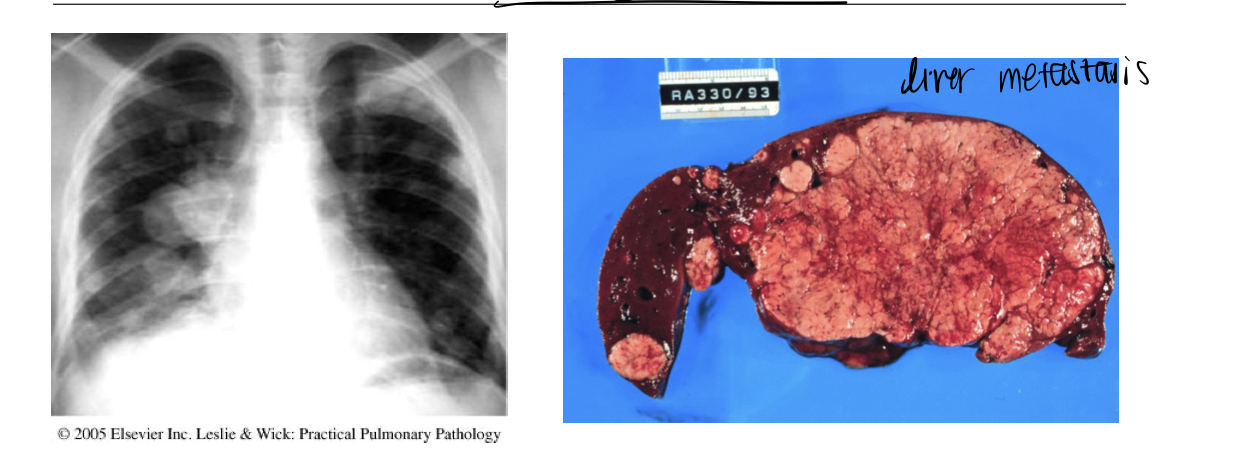

• 60F with small-volume hemoptysis for 2 weeks, has had a

worsened headache for the last week • Profile

• Current 40pack-yr smoker • Current waitress • Meds/Allergies: none

• Vitals normal • ?Left supraclavicular

lymphadenopathy • Resp exam: hyperinflation • Normal CV exam • No abdo organomegaly

• Liver Function Tests

• ALT 55, Bili 18, Albumin 30

Mild Liver Enzyme Abnormalities

what type of cancer?

Squamous cell carcinoma

Adenocarcinoma

F>M